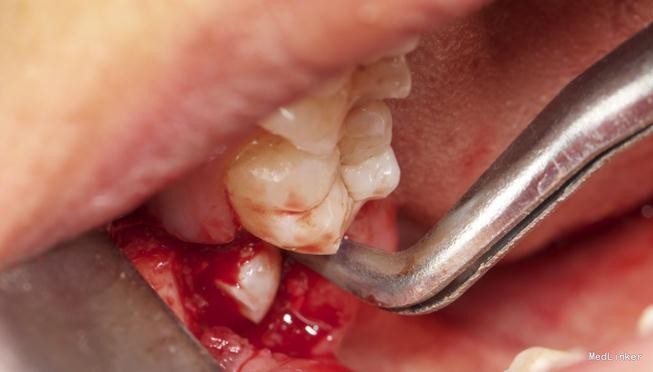

患者,男,25岁,要求拔除左下颌水平阻生牙齿,平素体质一般,无药物、食物过敏史,无高血压、心脏病等系统病史

拔除术

挺好的病例,图片也很清晰,牙齿分的很好,我之前拔过类似的牙,牙齿分开后近中撬不动,最后又T型分开近中后才弄出来

挺好的且较常见的病例,最主要的是照片很清晰!在拔出了阻生齿后,患者的对颌牙是不是应该同时或者择日拔除呢,对颌牙伸长很快的……

水平阻生拔除的难度还是很大的,图片看着创伤不是很大,能不能把您拔牙时的阻力分析和该牙具体的拔牙步骤给我们说一下呢?谢谢~